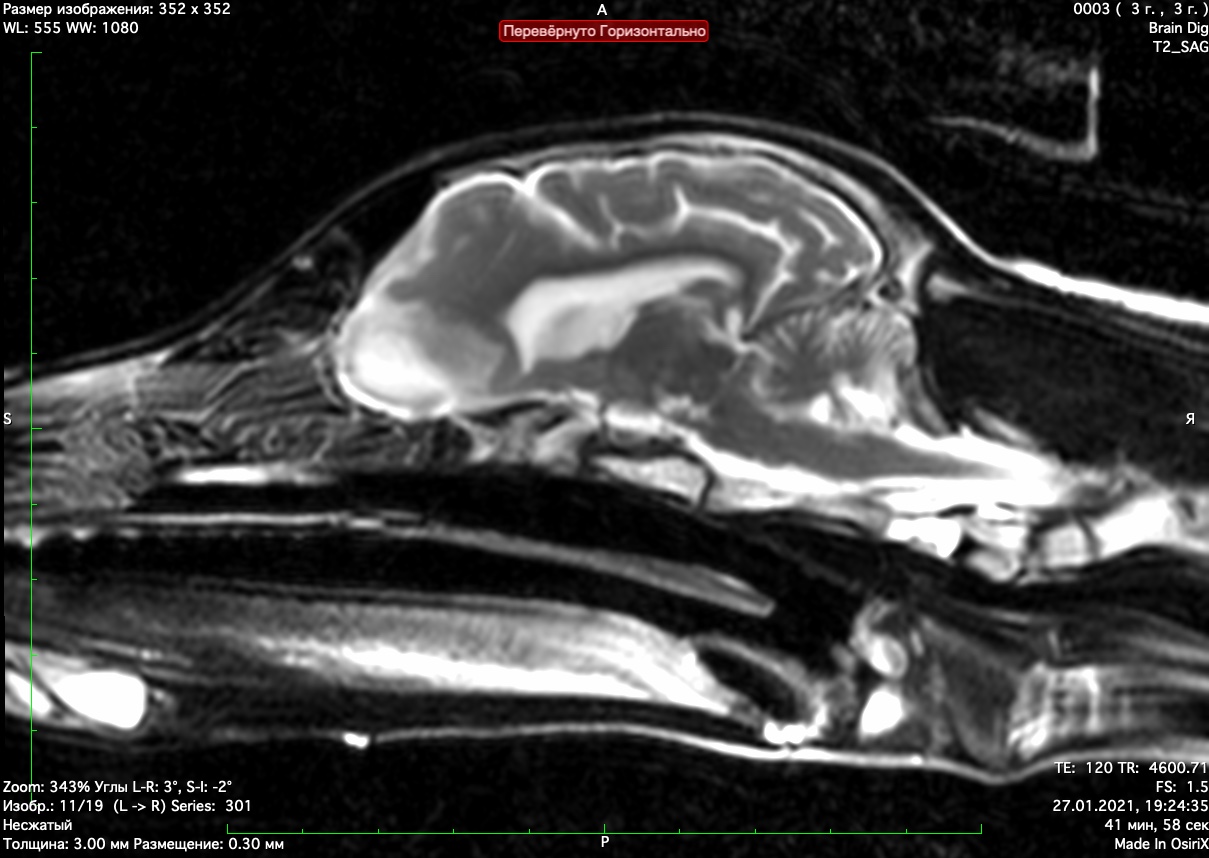

При проведении мрт диагностики установлено признаки атрофии коры голов головного мозга и мозжечка нарушение дифференциации между серым и белым веществом головного мозга. Признаки кровоизлияний в коре головного мозга

Данные изменения характерны для болезней накопления